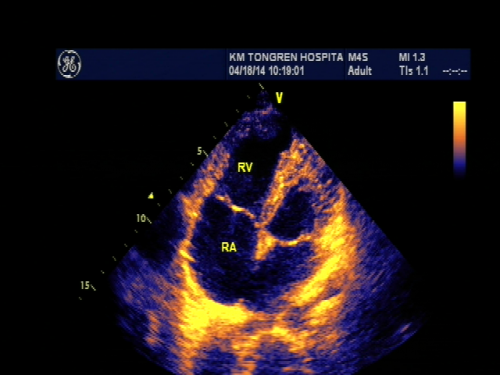

用于各种先天性、后天性心脏病患者的诊断、治疗及术前检查和术后追踪,风湿性心脏病患者的术前检查及术后追踪,心脏听诊有杂音者,心肌炎、高血压、冠心病、肿瘤、心功能不全,感染性心内膜炎、心肌病、心包膜疾病患者,川崎病的冠状动脉检查及追踪,先天异常或染色体异常而可能合并有心脏疾病者如唐氏症等,其它系统器官疾病所导致的心脏功能异常者如甲状腺功能亢进、尿毒症、肿瘤侵犯等。另外,对于有以下症状者,如原因不明的胸痛或心绞痛患者,心律不齐而有明显自觉症状或心脏扩大者,难以用呼吸系统疾病解释的呼吸急促、心跳过快、发绀或心功能衰竭者,均应考虑作心脏超声检查。先天性心血管畸形是危害儿童健康的主要疾病之一,据近年国内文献报道,在出生存活的婴儿中先天件心血管畸形的患病率为0.1%~0.7%,国外报道为0.8%左右。本组疾病类型繁多,可有单一的结构异常,也可有多种畸形集合而成,临床表现复杂多样。超声心动图以其无创、直观、准确等诸多优点,成为小儿先心病的首选检查方法。我科刘志雄主任医师多次参加医院组织的地州小儿先天性心脏病筛查。

房间隔缺损

室间隔缺损